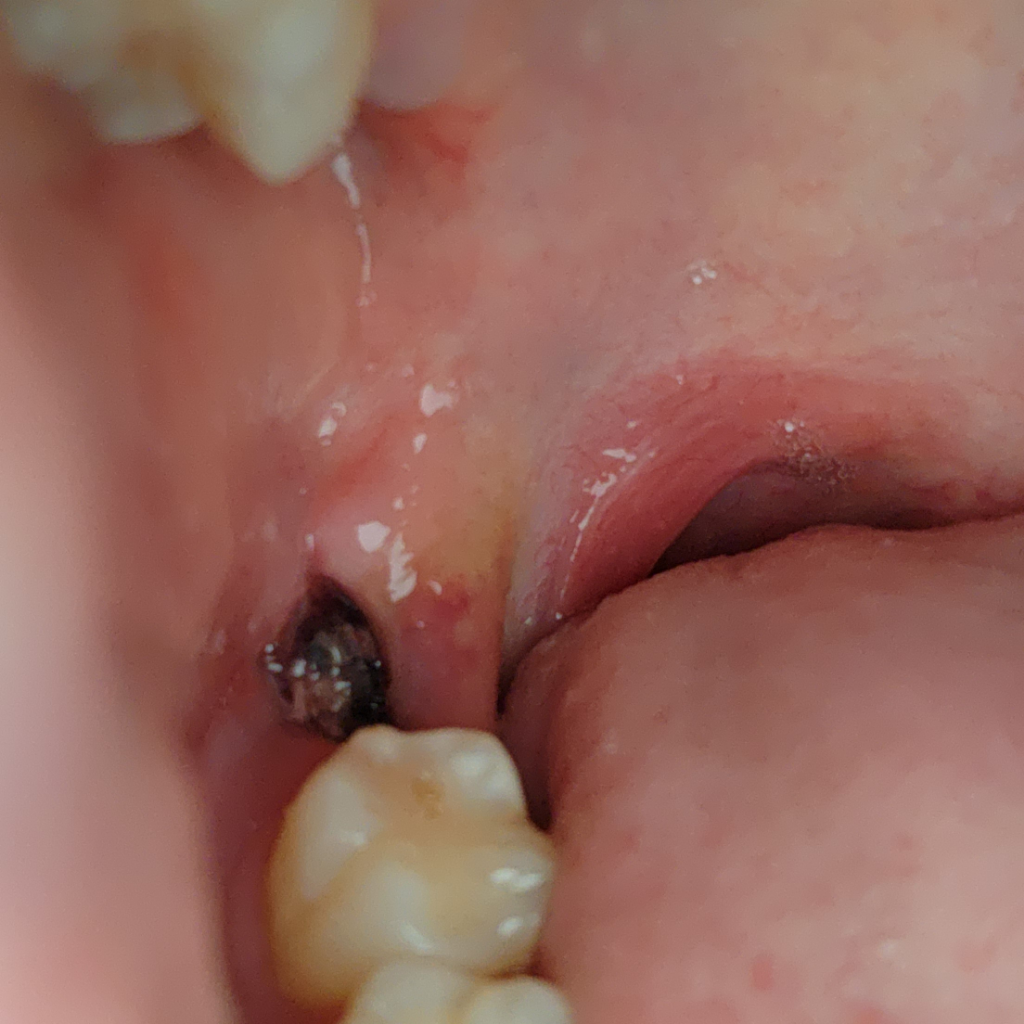

사랑니 발치 후 구멍에 이물질

사진이 징그러울 수 있습니다.

사랑니 발치 후 4~5일 정도가 지났는데 구멍에 뭔가

있어서 질문 올려봅니다 음식물 찌꺼기 일까요 거즈일까요 아니면 구멍이 채워지는 과정에서 자연스레 생기는건가요??

사진에 보이는 것은 혈병이나 발치와 내부에 생긴 가피로 보입니다 발치를 하게 되면 발치를 한 부위에 혈병이 형성되게 되는데이 혈병이 제거되거나 하면 발치한 부위가 치유되는 속도가 늦어질 수 있기 때문에 혈병의 제거되지 않도록 매우 조심히 관리를 하는 것이 좋습니다

실밥에 음식물이 껴서 그렇게 보이는거 같습니다. 많이 불편하시면 치과에 가셔서 소독한번 받아보시는게 좋을것같습니다.